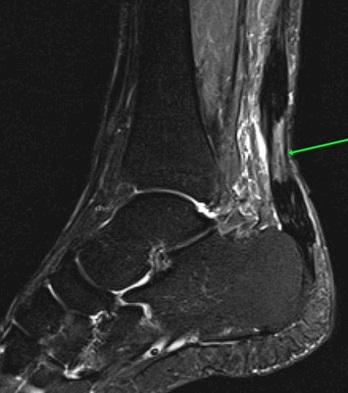

МР-признаки базисцервикального перелома шейки правой бедренной кости с наличием зон инфаркта головки и шейки правой бедренной кости, синовита правого тазобедренного сустава, отека окружающих мягких тканей справа.